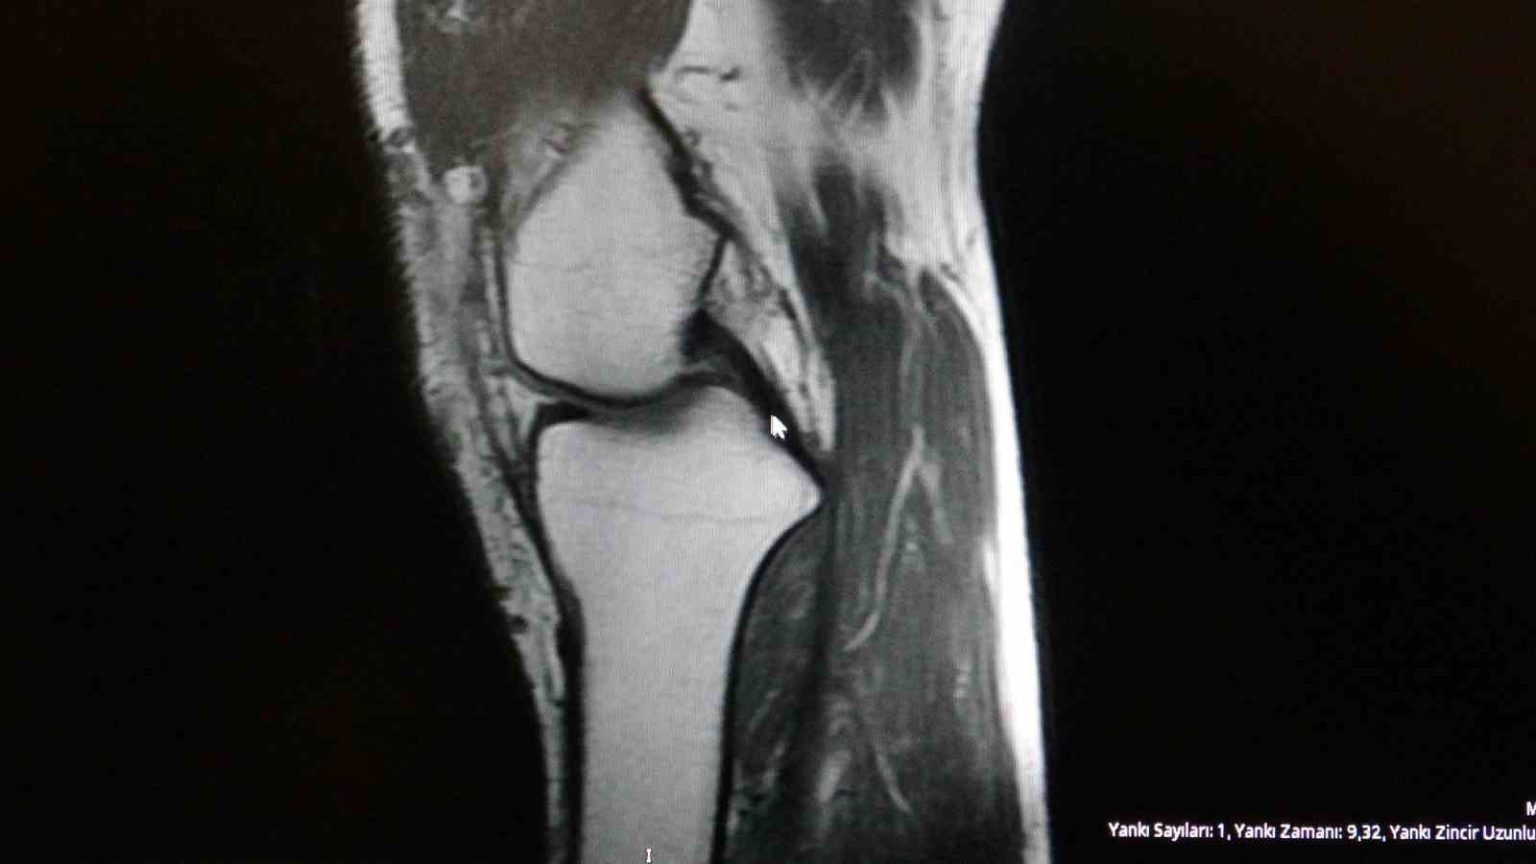

Ortopedi polikliniklerine en sık ayak bileği, diz ve omuz yaralanmalarıyla başvurulduğunu belirten Demirbaş, futbol nedeniyle yaralanma oranlarının da ilk sırada yer aldığını söyledi. Konuya ilişkin Demirbaş, “Futbolda menisküs yırtıkları, ön çapraz bağ yırtıkları, iç ve dış yan bağ yaralanmaları, aşil tendon kopmaları ve ayak bileği bağ yaralanmaları çok sık görülüyor. Ayrıca spora bağlı kırıklar da önemli bir yer tutuyor” ifadelerini kullandı.